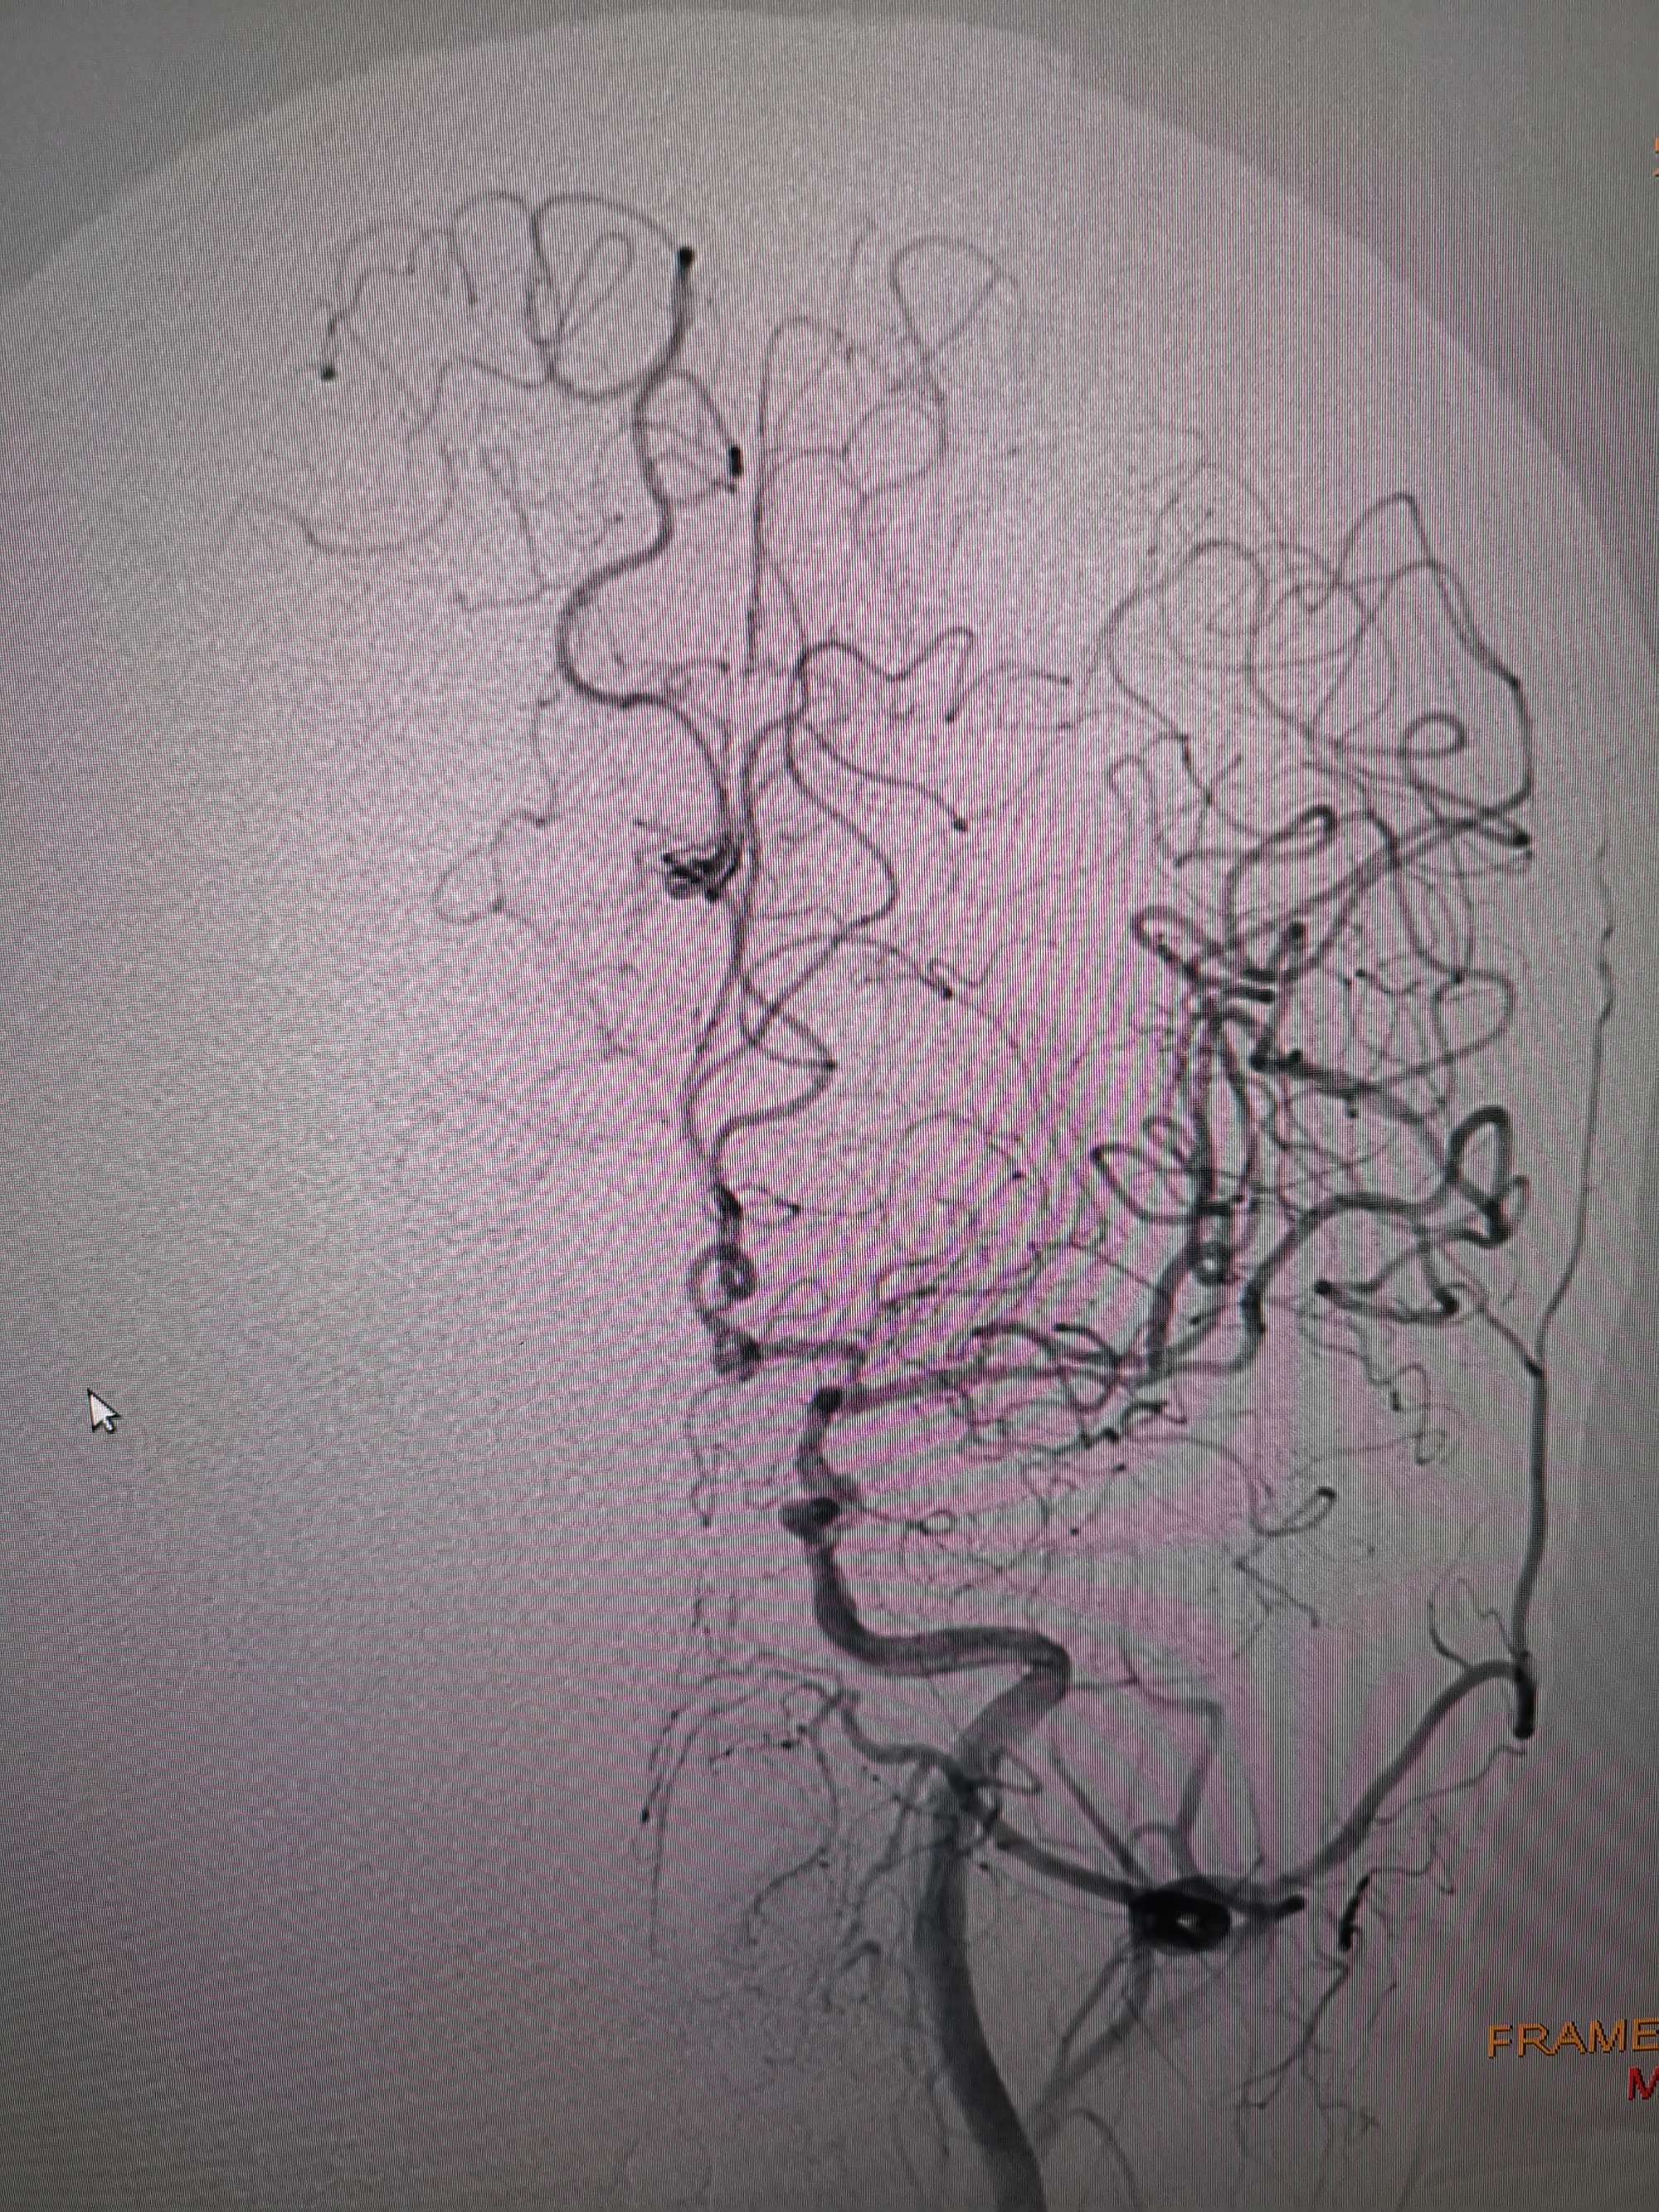

入院造影影像

术前再次造影评估

右侧椎动脉穿支供血及左侧PICA供血较入院时略有改善,但改善不明显。故按计划行左侧椎动脉再通术